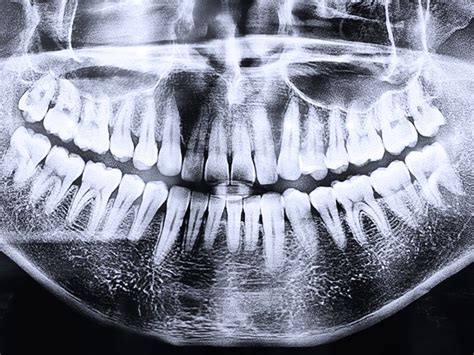

Son técnicas de diagnóstico por imagen en odontología en las que el sensor o película radiográfica se coloca fuera de la boca del paciente. Es fundamental para los análisis cefalométricos que determinan la posición y alineación de los dientes, así como la relación entre los maxilares y el cráneo.

Por ejemplo, podríamos realizar una ortopantomografía o radiografía panorámica dental, que es una radiografía que muestra las mandíbulas, los dientes y los tejidos que rodean esta zona.